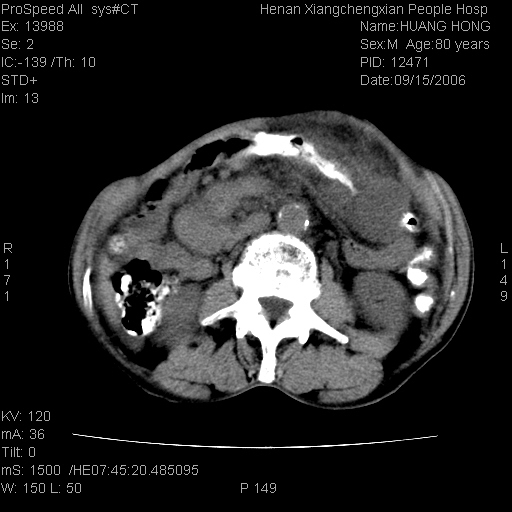

患者, 男, 80岁, 发现上腹部包块1年余,无其它不适.2006-9-14ct片是喝水后扫描2006-9-15ct片没喝水扫描![]() ![]() ![]() ![]() ![]() ![]() ![]() ![]() ![]() ![]() ![]() ![]() ![]() ![]() ![]() ![]() 以上是喝水片 以下是空腹片 ![]() ![]() ![]() ![]() ![]() ![]() ![]() ![]() ![]() ![]() ![]() ![]() ct:胰腺前方、肝脏与胃之间可见巨大类圆形囊性低密度影,大小约152mmx145mmx118mm,上缘平t11椎体上缘,下缘平l3椎体下缘,密度均匀,ct值15hu,其内呈多房分隔,囊壁薄且光滑,边界清晰,周围组织及器官明显受压。肝脏实质内未见异常密度影,胆囊未见异常,胰腺密度未见异常,脾脏大小、形态及密度未见异常,腹膜后间隙未见肿大淋巴结影。 印象:胰腺前方、肝脏与胃之间巨大类圆形囊性低密度影.性质待定。多考虑:.肠系膜巨大囊肿。 守望可可西里发言:支持楼主,考虑肠系膜囊肿,多为小肠系膜。 ysxyy发言:我总觉得这个病人虽然很像肠系膜囊肿,但还是应该强化一下; 下面这几幅图里肿块和主动脉的关系不太清,不知能否除外血管性来源? ![]() ![]() ![]() 病理结果:横结肠系膜间叶瘤.部分区域间质细胞增生活跃. 病理图片 ![]() 良性间叶瘤:是指由两种或两种以上的间叶组织所构成的混合性肿瘤.肿瘤仅发生在腹膜后和肠系膜,.前者较后者多发.良性间叶瘤常发生在肾或四肢,腹膜后较少见,各年龄均可发病.女多与男,预后较好,但术后易复法. 恶性间叶瘤:由两种以上恶性间叶组织成分组成. 光镜:肿瘤由脂肪/血管/平滑肌构成. 原贴地址: http://www.radinet.com.cn/forum_view.asp?forum_id=4&view_id=16217 ok |